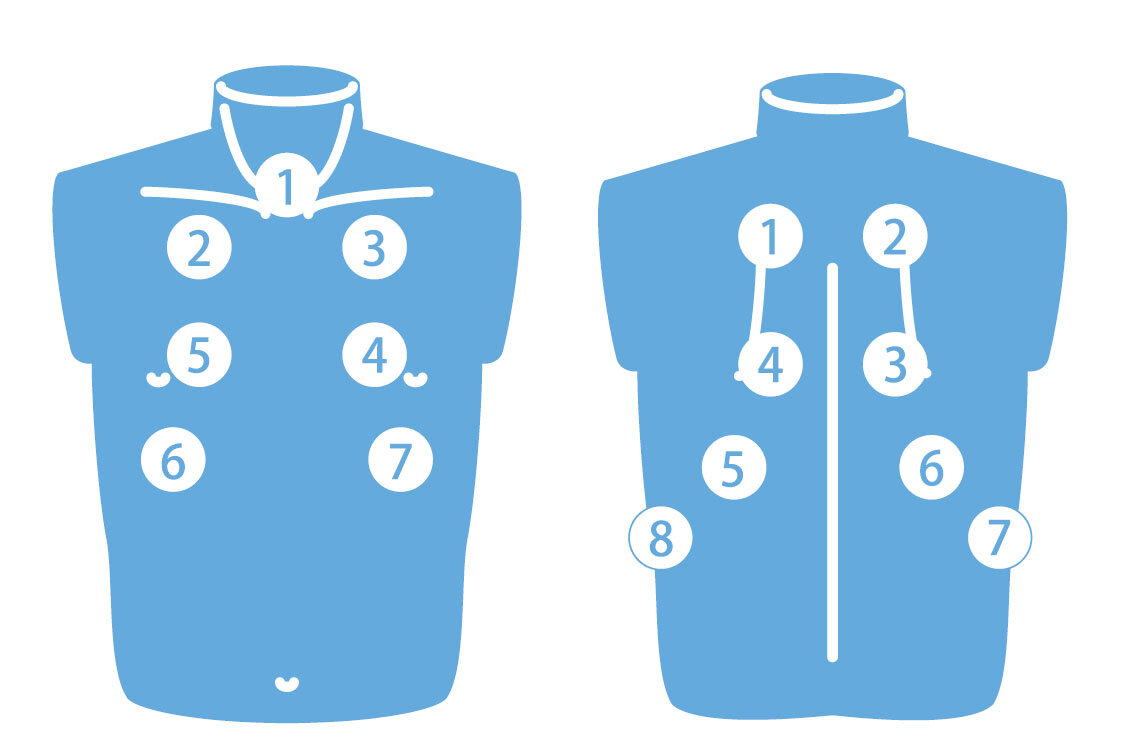

左:前胸部 右:背部

左:前胸部 右:背部

前胸部:1. 気管/2. 右上肺野/3. 左上肺野/4. 左中肺野/5. 右中肺野/6. 右下肺野/7. 左下肺野

背 部:1. 左上肺野/2. 右上肺野/3. 右中肺野/4. 左中肺野/5. 左下肺野/6. 右下肺野/7. 右助骨横隔膜角/8. 左助骨横隔膜角